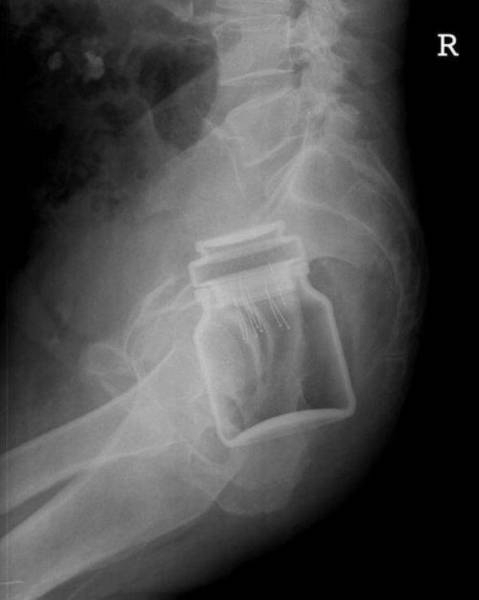

İÇİNDEKİ ŞEYE RÖNTGEN UZMANLARI ŞOK OLDU!

,Dünyada çekilen bu röntgenler hem röntgen uzmanlarını hemde görenleri şok ediyor...